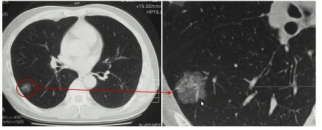

所谓肺磨玻璃结节,是指在高分辨率CT扫描上表现为其内支气管及血管纹理可显示的密度轻度增高影。

肺部磨玻璃结节(ground glass nodule, GGN)是指计算机断层扫描(computed tomography, CT)上边界清楚或不清楚的肺内密度增高影,其病变密度不足以掩盖其中走行的血管和支气管影。

磨玻璃结节是局限性的肺内磨玻璃密度影,肺内磨玻璃密度影是由气腔部分充盈、肺间质增厚、肺泡的部分塌陷、肺毛细血管血容量的增加等多种因素综合导致的,CT表现为密度轻度增高但其内血管及支气管轮廓尚可见。